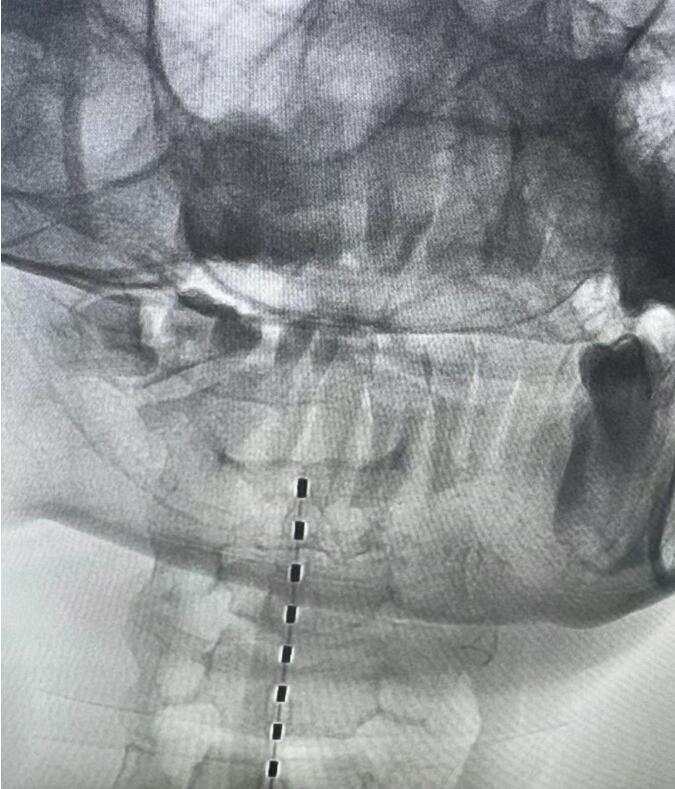

手术中,团队凭借丰富的功能神经外科经验,通过微创方式将短程刺激电极精准植入患者颈段脊髓的硬脊膜外。电脉冲由此发出,温和而持续地刺激上行性网状激活系统——这是维持大脑觉醒与意识的关键通路。整个手术历时约30分钟,过程平稳,患者生命体征始终稳定。